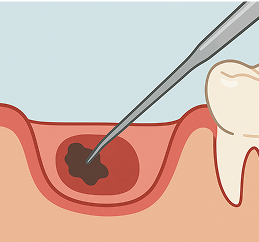

歯の神経や感染部分を取り除く根管治療が必要となります。

歯科用CTを用いることで、歯や根管の状態を3次元的に把握できます。根管の形やサイズは個人差があり、CTによって正確な情報を得ることで、より精密に治療できます。

根管治療後の再発率は約30〜70%といわれています。根管の先端は直径0.25mm程度と非常に細く、精密な処置には専用の機器や設備が欠かせません。

たかた歯科医院では、精度の高い根管治療を行うために、以下のような取り組みを行っています。